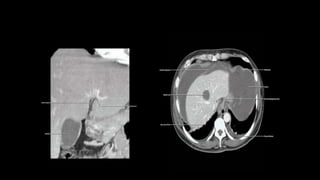

• On unenhanced CT normal liver parenchyma has homogeneous

density, which can vary between 55 and 65 HU.

• Exceeds that of the spleen by about 10HU.

• Increased diffuse deposition of fat leads to reduction in attenuation

• Increased glycogen – increased attenuation

• Hepatic perfusion cycle can be differentiated into three phases.

1. Arterial phase

2. Redistribution or portal venous phase

3. Equilibrium or hepatic venous phase

Bolus tracking is done and when aortic enhancement reaches a

threshold of approximately 150HU, hepatic scanning is initiated.

• Early arterial phase – Approx 10 sec after contrast threshold based

scanning initiation.

Contrast enhancement of the abdominal aorta and hepatic artery

without admixture of enhanced portal venous blood

• Late arterial phase : Approx 20

sec after scanning initiation.

- Clear depiction of hepatic artery

and its branches.

- Minimal admixture of enhanced

portal venous blood

• Redistribution/ portal venous

inflow phase : About 30 sec after

scan initiation.

- Allows early visualisation of

portal vein and its intrahepatic

branches.

- Maximum contrast enhancement

after 40sec.